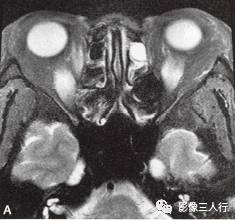

A~C.抑脂T2WI横断面;D~F.T1WI横断面;G~H.T1WI冠状面;I.抑脂T2WI冠状面

横断面显示双侧眼球明显突出,双侧眼球角膜至双侧颧突连线的垂直距离分别为:右侧2.2cm、左侧2.3cm。双侧眼外肌明显增粗,以双侧内、外、上、下直肌明显,短径均可达7mm,且以肌腹增粗明显呈梭形,T1WI等信号(图D~F,图G~H),抑脂T2WI呈明显高信号(图A~C,图I)。双侧眼眶内及球后脂肪增多,双侧眼球内侧至眼眶内侧壁的脂肪厚度增宽。双侧视神经形态及走行正常,双侧眼球晶体、玻璃体形态及信号正常。

影像学检查可帮助该病的诊断与鉴别诊断。CT表现为眼外肌增粗,主要为肌腹增粗,附着于眼球壁上的肌腱不增粗,少数也可同时累及眼外肌肌腹和肌腱。最常累及下直肌,其次为内直肌、上直肌和上提肌,偶尔累及外直肌。MRI表现为受累的眼外肌T1WI低信号,T2WI高信号,压脂T2WI为高信号;晚期眼外肌已纤维化,在T1WI和T2WI均呈低信号。增强扫描急性期时增粗的眼外肌有轻至中度强化,晚期眼外肌纤维化时则无强化。眶内脂肪体积增多表现为球周脂肪尤其是眶前部脂肪的增多。本例影像征象较典型。